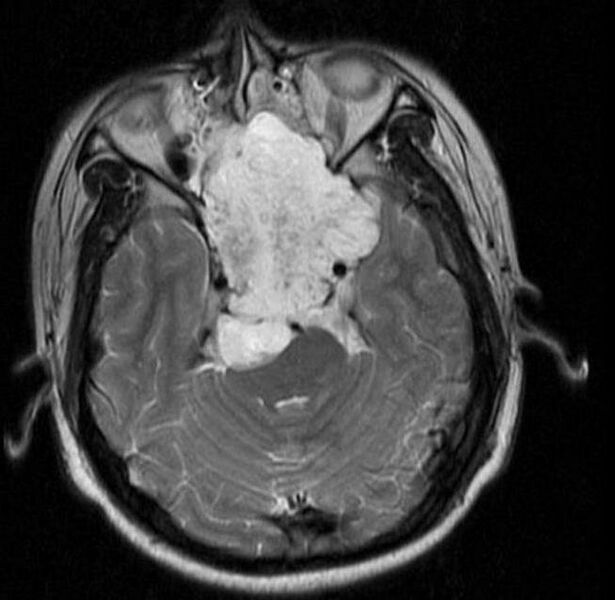

Description MRI of extensive clival chordoma in 17-year old male patient, axial view. Tumor in the nasopharynx extending from nasal cavity to brainstem posteriorly is clearly visible.

Source Hassan S, Abdullah JM, Wan Din SJ, Idris Z. Combined use of maxillomandibular swing approach and neurosurgical ultrasonic aspirator in the management of extensive clival chordoma: a case report. Journal of Medical Case Reports. 2, 49. 2008. doi:10.1186/1752-1947-2-49. PMID 18279530.